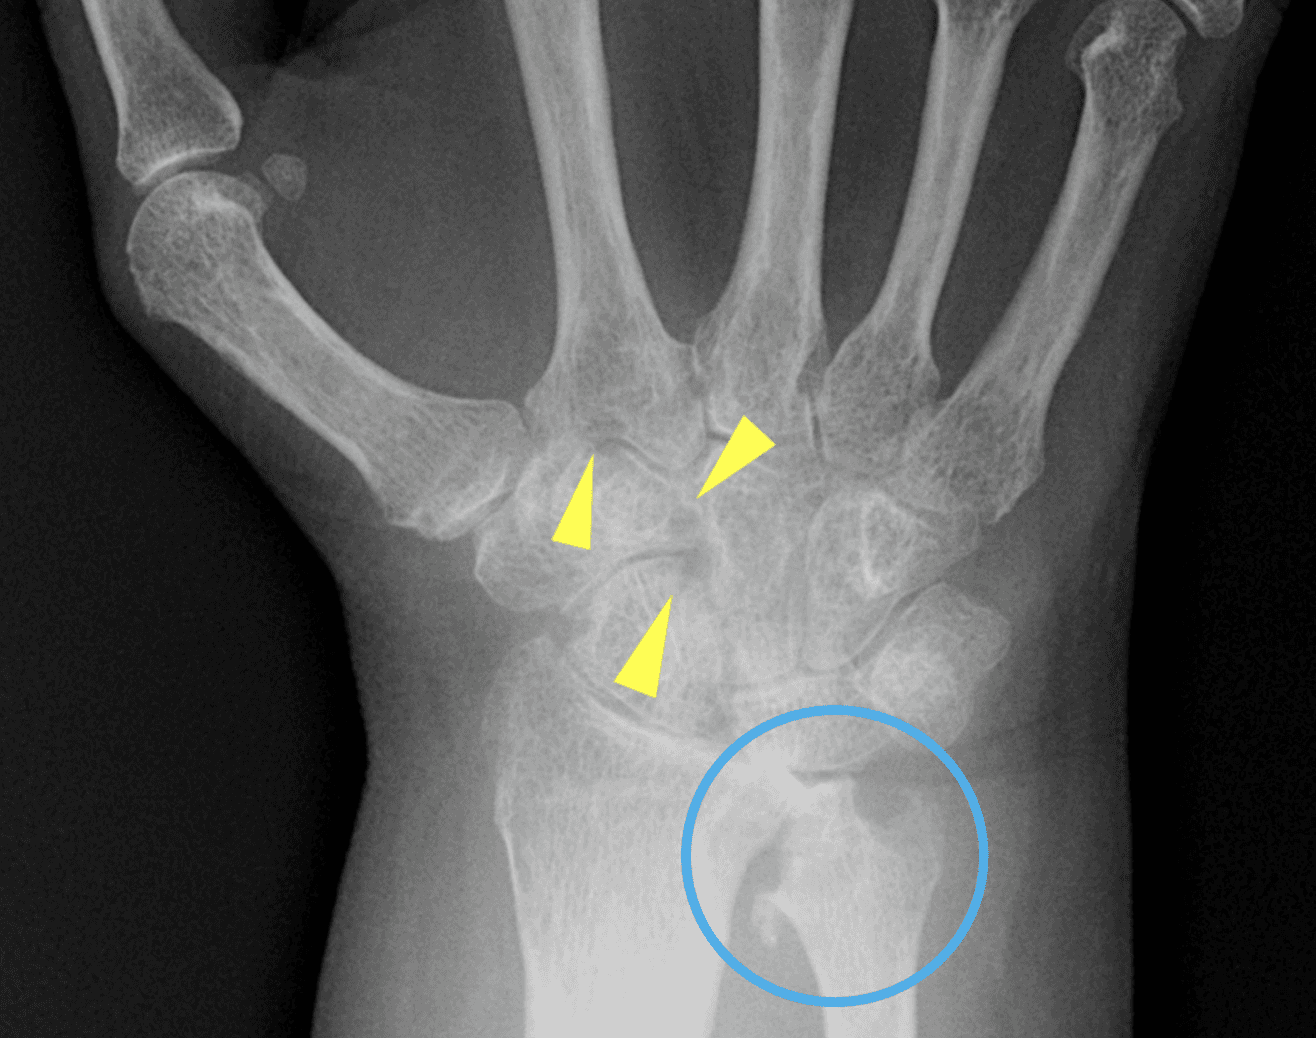

En artritis reumatoide, el patrón clásico combina tumefacción fusiforme y simétrica de partes blandas, osteopenia yuxtaarticular, erosiones marginales tempranas en cabezas metacarpianas y bases proximales de falanges, progresión a pinzamiento articular uniforme y deformidades por inestabilidad ligamentaria, como subluxación cubital en MCP. La preservación relativa de las articulaciones DIP es una pista mayor. En artritis psoriásica, por el contrario, la mineralización suele mantenerse, predominan las interfalángicas, la dactilitis aparece en cerca del 25% de los pacientes y las erosiones marginales progresan a deformidad tipo pencil-in-cup; además, la periostitis y la proliferación ósea ayudan a separarla de artritis reumatoide. La osteoartrosis erosiva, frecuente en mujeres mayores de 60 años, muestra erosiones centrales con configuración en gull-wing o seagull, con afectación predominante de DIP y respeto habitual de MCP. La artropatía por CPPD introduce otro lenguaje: condrocalcinosis en fibrocartílago triangular y ligamentos del carpo, osteofitos en gancho en la segunda y tercera cabezas metacarpianas y cambios degenerativos en una distribución no típica para osteoartrosis primaria. La gota, en cambio, combina masas de partes blandas por tofos, mineralización conservada, erosiones bien definidas con borde escleroso y márgenes colgantes; además, los cambios radiográficos pueden tardar en aparecer en promedio entre 7 y 10 años. Finalmente, el lupus eritematoso sistémico suele manifestarse con subluxaciones y deformidades reducibles sin erosiones, mientras que en esclerosis sistémica la acroosteólisis y las calcificaciones de partes blandas dominan la imagen.

La tabla comparativa del artículo resume una idea central: cada entidad tiene una geografía preferente. La artritis reumatoide predomina en MCP y carpo, con afección inusual de las DIP; la artritis psoriásica compromete sobre todo interfalángicas y con frecuencia las DIP; la osteoartrosis erosiva se concentra en interfalángicas, especialmente DIP; la CPPD favorece MCP y radiocarpiana en una distribución “incorrecta” para osteoartrosis primaria; la gota puede ser poliarticular asimétrica con masas tofáceas y erosiones bien definidas; y el lupus típicamente produce deformidad sin erosión. En otras palabras, el primer paso del diagnóstico diferencial no es la erosión, sino el mapa articular.